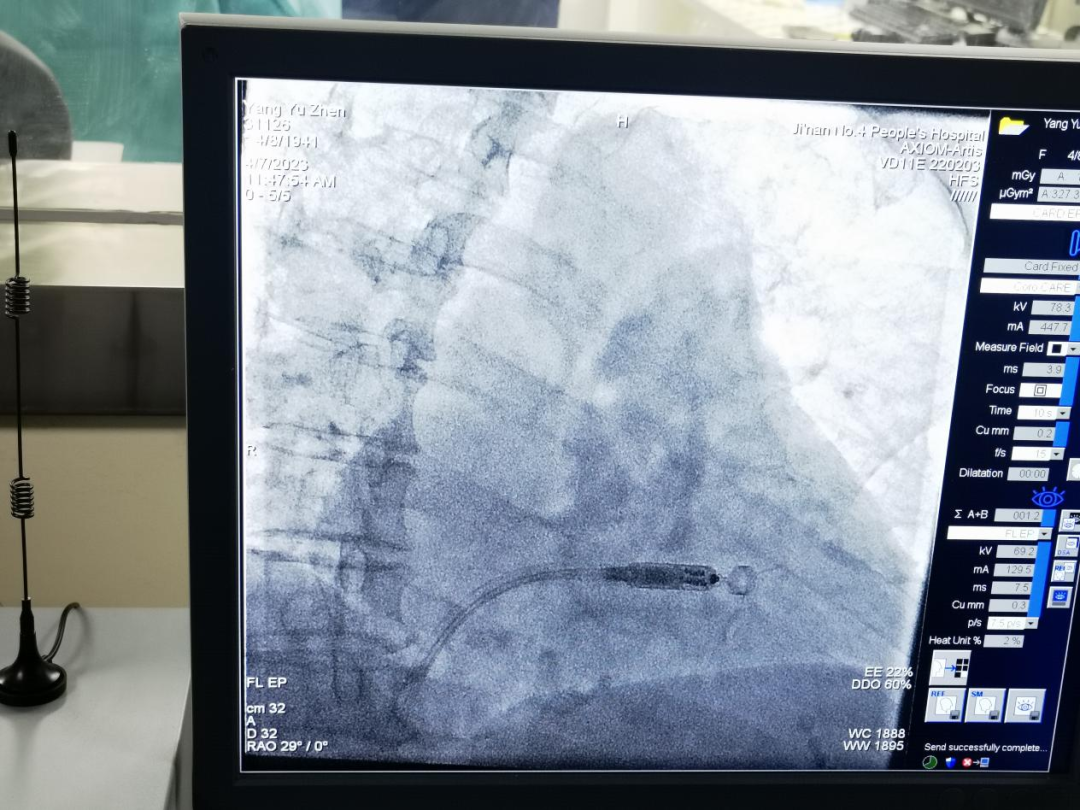

2023年4月7日,济南市第四人民医院心血管内二科李晓梅主任团队成功完成医院首例无导线起搏器植入术,再次将医院心律失常介入诊疗水平带入更高领域。

该患者为81岁高龄的老年女性,近2年反复头晕、胸闷,经检查发现为持续性房颤伴长间歇,具有起搏器植入指征。但考虑到患者高龄,安装传统起搏器,手术过程痛苦,术后感染风险高,经过李晓梅主任的慎重考虑,结合患者的术前各项化验检查,建议该患者选择无导线起搏器,仅仅40分钟顺利完成该手术。患者术后12小时即可下床,2天后出院。

无导线起搏器类似胶囊大小,又名胶囊起搏器,重量仅有2g。术中仅需要穿刺股静脉,通过鞘管将起搏器送入右心室,起搏器寿命可达10余年,且兼容磁共振。无需放置起搏导线,没有切口,避免了导线相关的并发症,比如导线脱位、囊袋感染,术后疤痕等,而且术后恢复快,无需拆线,大大缩短了患者的住院时间。